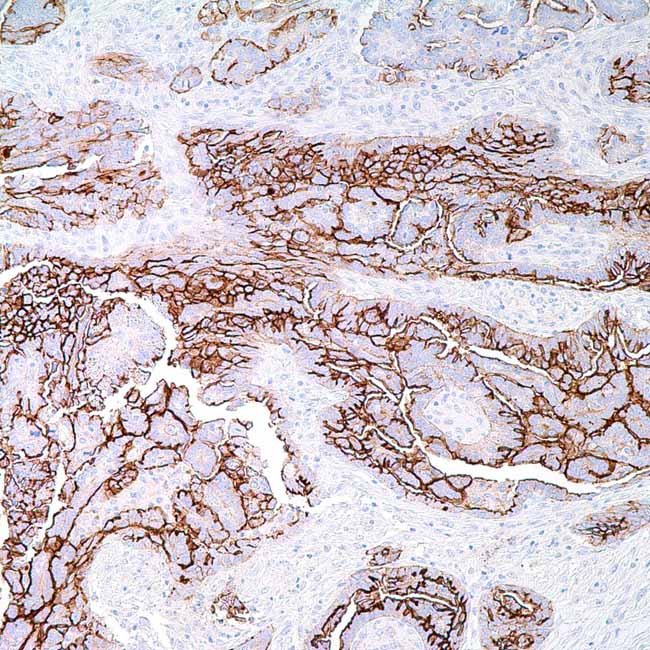

CA-125 (OC125)

CA-125 (Cancer Antigen 125), encoded by the MUC16 gene,is a high molecular weight transmembrane glycoproteinbelonging to the mucin family. It is not expressed in normalovarian surface epithelium but is detected in tissues suchas cervix, endometrium, and fallopian tube epithelium.Pathologically, CA-125 shows strong and diffuse expressionin the majority of ovarian serous carcinomas and inepithelioid mesotheliomas, making it an importantresearch marker for gynecologic malignancies. CA-125immunostaining is also widely used in studies of tumorprogression and in validating biomarkers for ovarian cancermodels.

ControlOvarian serous carcinoma tissue